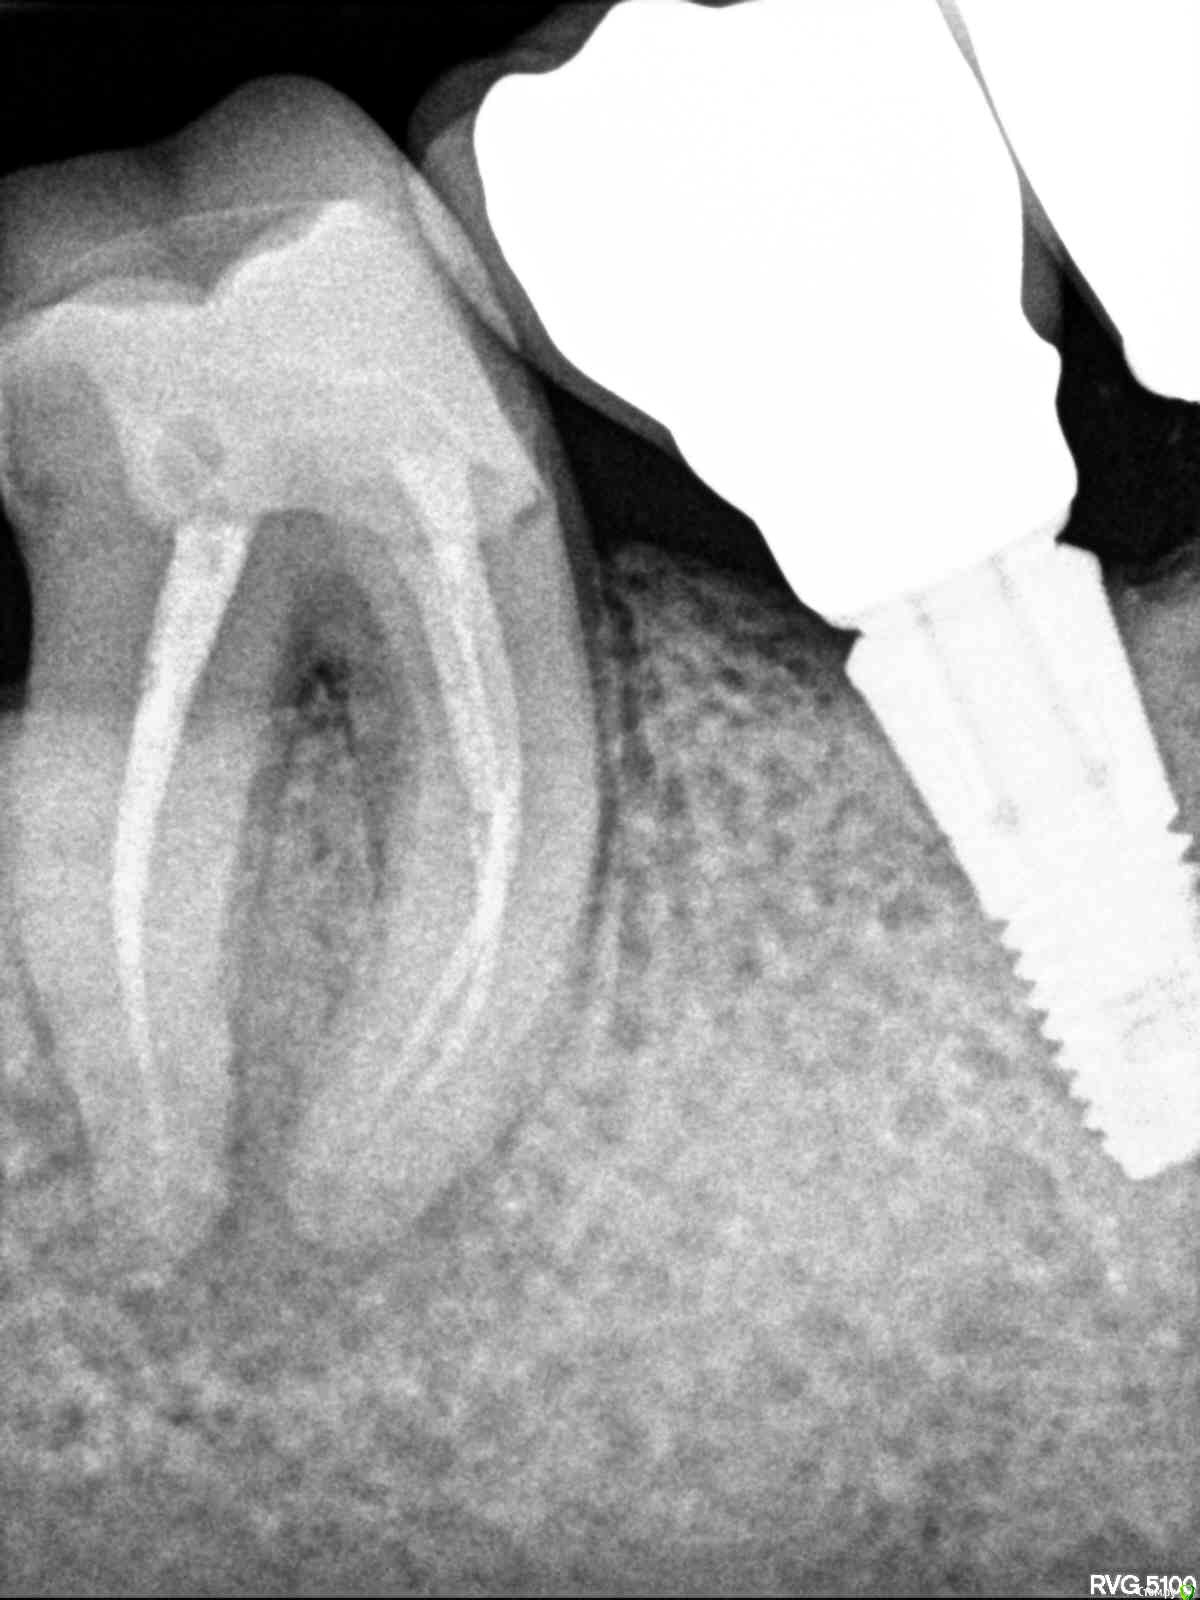

red_butler Опубликовано 27 октября, 2020 Поделиться Опубликовано 27 октября, 2020 Спасибо. В чем это выражается на снимке? Простите за настойчивость, просто врач, который отрицает периодонтит, как раз практикует его лечение, и успешно. Есть примеры. Вроде ей совсем нелогично отрицать этот факт. А вы бы посоветовали перелечивать или удалять? И если удалять, то устанавливать ли имплантат или нет? Снимок это негатив, в области верхушек корней и между корней просветление, это деструкция костной ткани. Периодонтит не видит доктор который лечил этот зуб?Для принятия решения нужен очный осмотр, если судить, только по рентгену то я за лечение. Ссылка на комментарий

лемурка Опубликовано 27 октября, 2020 Автор Поделиться Опубликовано 27 октября, 2020 (изменено) Снимок это негатив, в области верхушек корней и между корней просветление, это деструкция костной ткани. Периодонтит не видит доктор который лечил этот зуб?Для принятия решения нужен очный осмотр, если судить, только по рентгену то я за лечение.Нет, этот зуб был залечен давно в иной клинике. А этот доктор лечил другому родственнику периодондит, и вылечил успешно.Поэтому доктору нет никакого резона настаивать на том, что периодонтита нет. Ему вроде как выгодно как раз начать этот зуб лечить, но он считает, что лечить нечего... Изменено 27 октября, 2020 пользователем лемурка Ссылка на комментарий